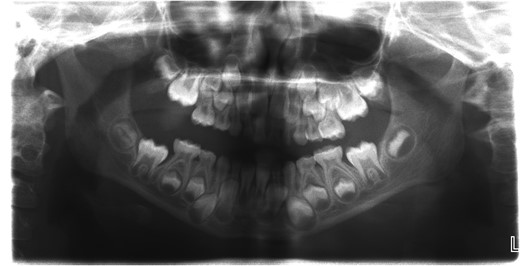

A 6-year-old girl presented to the Emergency Department with a suspected mandibular dislocation after falling off her scooter. She was previously fit and well with no significant medical history. She had complete restriction of all mandibular movements and trismus. The dental occlusion demonstrated a cross-bite with all the posterior teeth in contact and a mandibular asymmetry with the chin significantly deviated to the left side. Radiographic investigations (orthopantomogram (OPG) and postero-anterior (PA) mandible images) were performed but confirmation of the dislocation could not be determined on these views (Fig. 1). Consequently, a computerized tomography (CT) scan was performed that confirmed significant displacement of the condyle anteriorly and superiorly into the infratemporal fossa (Fig. 2). In addition calcification of the lateral and medial pterygoid muscles was noted on the affected side indicating chronic nature of the condition. Discussion with the patient’s general dental practitioner (GDP) revealed that the patient had a pre-existing dental malocclusion comprising of a cross-bite and mandibular asymmetry and this was also corroborated by a photograph taken well before the scooter accident. On this evidence it was therefore presumed that the condyle had been dislocated for many months or years and the scooter accident had only highlighted this. There were no other traumatic events of note in the history. The TMJ could not be convincingly reduced via a Hippocratic manoeuvre under a short general anaesthetic despite several attempts. In order to re-image the TMJ a magnetic resonance imaging scan was performed to prevent additional irradiation. This scan confirmed that the TMJ was still dislocated and had not been reduced. Due to the unsuccessful closed reduction, it was decided to perform an open reduction via a Risdon incision. When reduction with traction wires at the mandibular angle failed a bone hook was placed into the sigmoid notch and the dislocation was reduced using a fair degree of force.

Orthopantomogram (OPG) of the patient with longstanding dislocation.

This case highlighted that an OPG is not always adequate to confirm the diagnosis if clinically it is not clear that there is a dislocation, especially when it is chronic and the occlusion has developed to accommodate the new mandibular position. Longstanding TMJ dislocations tend to be more complex to treat. This is generally due to calcification of the pterygoid muscles [6]. Huang et al. proposed a treatment strategy classifying longstanding dislocations according to their duration. For dislocations <3 weeks, a closed reduction was proposed. For longstanding dislocations from 1 to 6 months open reduction with wide subperiosteal dissection and use of traction wires and retractors was suggested. For dislocations longer than 6 months, other additional techniques may be required including condylectomy, condylotomy, myotomy and arthroplasty [2, 7]. A chronically dislocated TMJ often results in changes to the occlusion and muscular posture, particularly in the growing patient. Consequently patients will require orthodontic assessment following initial management [8].

Longstanding dislocation of TMJ in paediatric population is very rare. One of the reasons may be underreporting due to the diagnostic pitfalls. The authors recommend that all children in whom the clinical diagnosis is in doubt should have a CT or an MRI scan. In paediatric population, OPG is not adequate for radiological diagnosis.